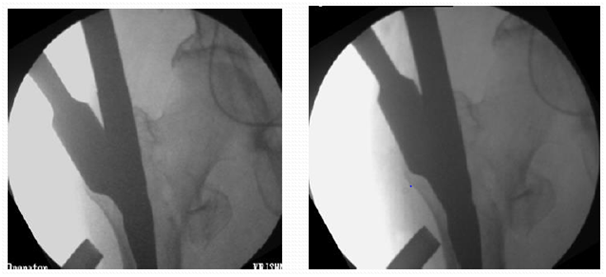

Proximal reaming must to accommodate broad proximal part of nail

1. Reamer to be pushed medially at entry point to break cortex so that reamer and nail is not displacing the fracture, as it leads to malposition of screws in head (Figure 18).

2. Reaming on guide wire up to the length and breadth of proximal part of nail up to lesser trochanter. Otherwise nail may not progress distally (Figure 19).

3. Reaming parallel to outer cortex/intact anterior or posterior cortex.

Figure 18 Cut a correct path. Reamer to hit lateral edge of proximal fragment for correct path.5

Figure 19 Proximal reaming must to accommodate broad proximal part of nail.